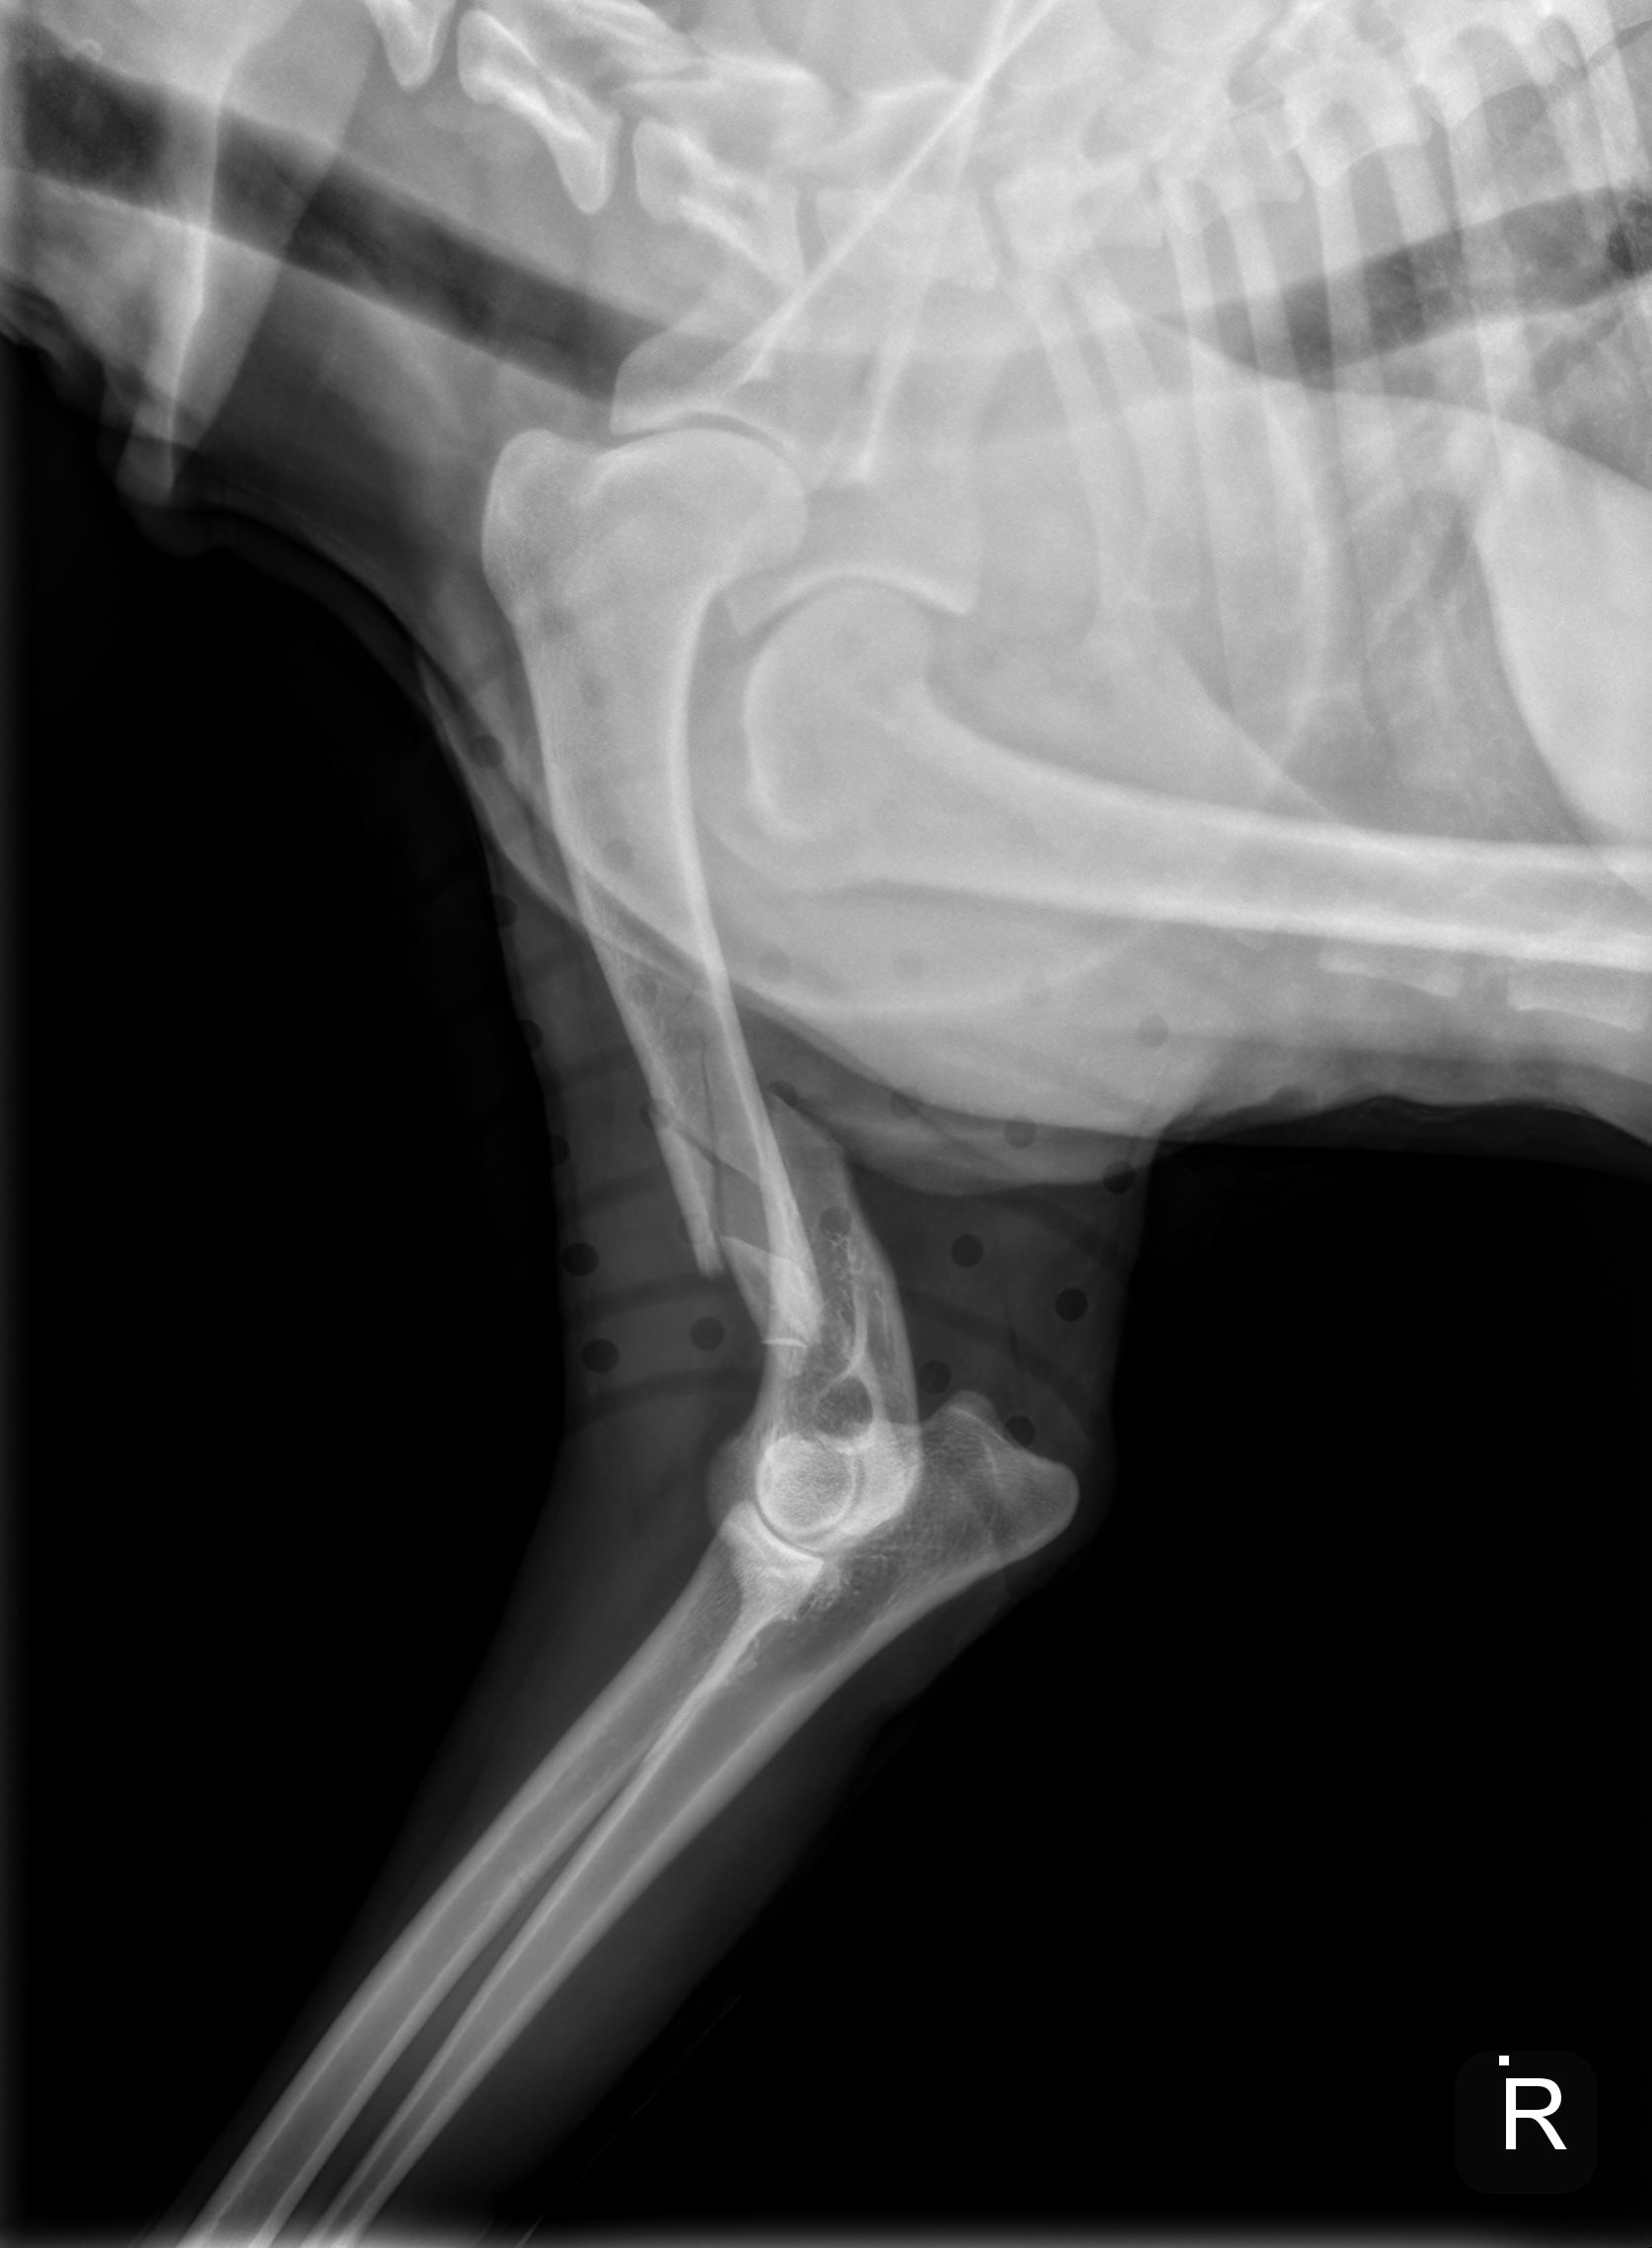

River is a sweet, gentle 1 1/2 year old golden, who had a tragic fall down a flight of stairs and fractured his humerus bone. Due to financial hardship and the physical challenges of navigating multiple flights of stairs, River’s family made the heartbreaking decision to surrender him to GRR so he could receive the care he desperately needed.

This type of injury is incredibly painful and requires specialized surgery to repair. Without it, River’s chances of ever walking, playing, or living a pain-free life are at risk. Watching him struggle to stand and looking into his eyes as he winces in pain is heartbreaking.

On Tuesday (10/30/2025) afternoon, his leg was surgically repaired using plates, screws & pins.  We are hoping his will be fully recovered in 8 weeks.